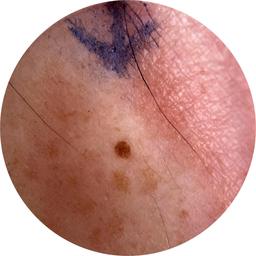

ISIC_5706752

Clinical

Field Value

acquisition_day 264

age_approx 55

anatom_site_1 Lower extremity

anatom_site_general lower extremity

concomitant_biopsy False

diagnosis_1 Benign

diagnosis_confirm_type single image expert consensus

family_hx_mm False

fitzpatrick_skin_type I

image_manipulation instrument only

image_type dermoscopic

lesion_id IL_0266048

patient_id IP_7932723

personal_hx_mm True

sex male